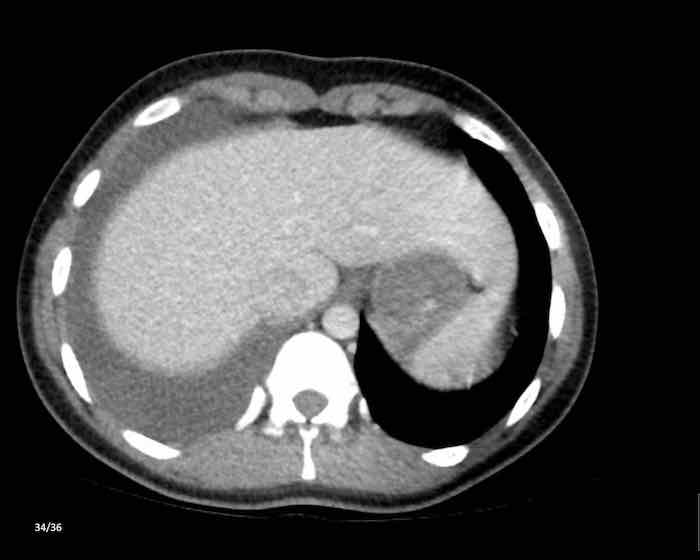

Các hình ảnh này của một phụ nữ 65 tuổi có tiền sử mắc bệnh Graves, một rối loạn tự miễn liên quan đến tình trạng cường chức năng tuyến giáp.

CT được thực hiện vì lý do ho ra máu.

Hình ảnh

Có một tuyến ức to lớn, cồng kềnh chứa mô mỡ đại thể.

Đây là hình ảnh điển hình của tăng sản tuyến ức.

Tăng sản tuyến ức trong bệnh Graves có liên quan đến tình trạng dư thừa hormone tuyến giáp và kháng thể kháng thụ thể thyrotropin.

Tình trạng này thường cải thiện sau khi điều trị thành công bệnh Graves.